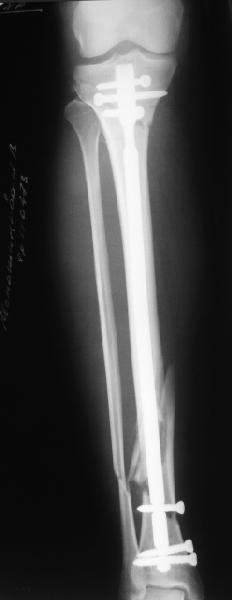

Проксимальный и дистальный переломы tibia

Направили к нам пациентку 35 лет с переломом дистального отдела костей голени.

У нас сделали снимок сзахватом обоих суставов - еще и проксимальный метафиз сломан. Чем бы у вас фиксировали такой перелом? Как его правильно закодировать по классификации АО?

Можно либо как два перелома - 41A+42B. А можно как один сегментарный 42С.